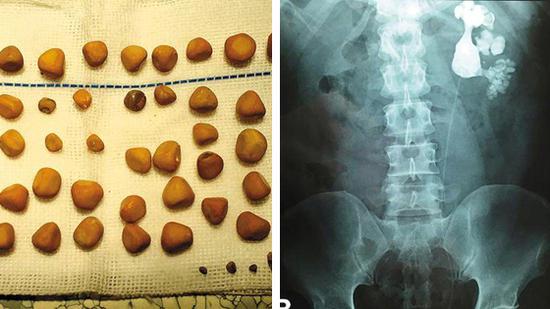

最近,新桥医院泌尿科冯医生一个月就做了20多台结石手术。前段时间,他在一位五旬男子的身体里取出了143颗结石,手术难度非常大,好在手术很成功。陈先生今年56岁,经常腹部胀痛,20多岁时疼得厉害,每次疼痛发作他就扛着,去村里的卫生所输个液后得到缓解。

陈先生的儿子陈帅(化名)住在城里,知道父亲有这个毛病,前段时间,他带父亲去新桥医院做B超检查,片子上显示他体内长了结石,形状像鹿角一样。当时,陈先生不敢相信,对检查结果持有怀疑态度。最终,陈先生在儿子的劝导下做了手术,医生取出了143块结石。

“病史太久,陈先生的病是拖出来的!”新桥医院泌尿外科副主任医师冯嘉瑜告诉记者,像陈先生这样严重的病人,他每个月都会碰到一两个,多数来自农村,长期不治导致结石越来越大。